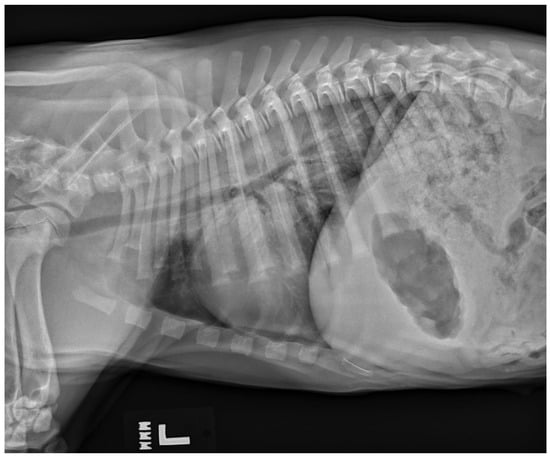

6.6. Neurogenic Pulmonary Edema